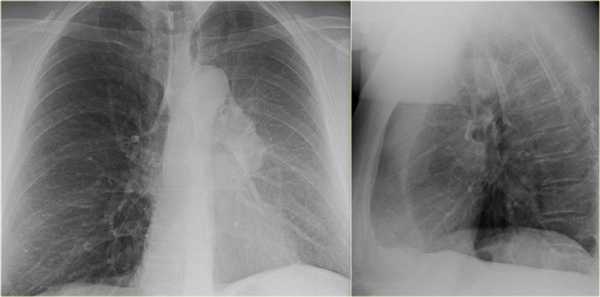

Ателектаз средней доли правого легкого.

- Симптом силуэта — нечеткие границы правых отделов сердца.

- Трехгранные изменения высокой плотности, визуализирующиеся на боковой рентгенограмме, являются результатом ателектаза средней доли правого легкого.

При ателектазе средней доли правого легкого подъем диафрагмы навсегда значительно выражен.

Ателектаз нижней доли правого легкого.

На нижепредставленой рентгенограмме пациента 70 лет, упавшего с лестницы, в плевральной полости определяется скопление жидкости, предположительно являющейся кровью.

Это ателектаз нижней доли правого легкого.

Обратите внимание на правую границу сердца. Правая междолевая артерия не видна потому, как она не окружена воздушной легочной тканью, а закрыта спавшейся нижней долей правого легкого.

Ниже представлены последующие рентгенограммы органов грудной полости того же пациента, на которых ателектаз разрешен.

Обратите внимание на правую междолевую артерию (красная стрелка) и границы правых отделов сердца (синяя стрелка).